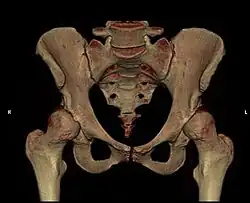

- Beckenanatomie

Anatomie des gesunden Beckens (Ansicht von vorne) -

Modell eines gesunden Beckens

Das Becken ist der Mittelpunkt des menschlichen Körpers und vereinigt die Wirbelsäule mit der unteren Extremität (Bein). Gleichzeitig liegen wichtige Organe, wie z. B. die Harnblase, der Enddarm, die Geschlechtsorgane und deren Anhänge, direkt im Beckengewölbe. Große Gefäße und Nerven (Ischiasnerv, Beckenarterie und -vene) gabeln sich hier. Schließlich setzen zahlreiche Muskeln, Sehnen und Bänder am Becken an, die für die Körperstatik und besonders für die komplexen Hüftbewegungen wichtig sind.

Die gewölbeartige Struktur des Beckens und die empfindlichen Weichteilverhältnisse (Nerven, Gefäße, Muskel-Sehnenansätze) machen die Zugangswege kompliziert.